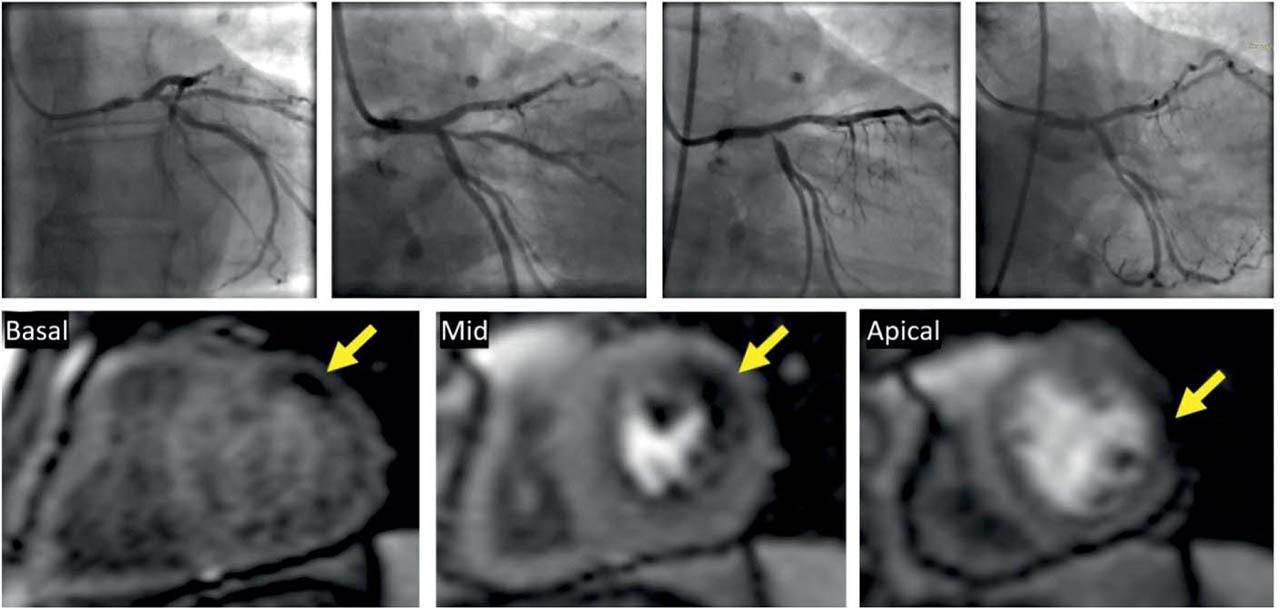

Figure 3